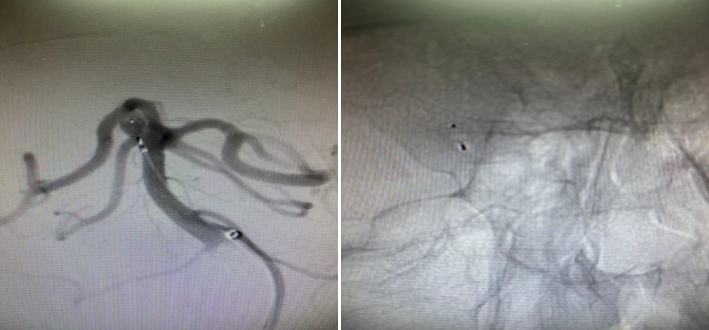

经过周密的术前检查,在蒲军主任的指导下,黄晓斌及张明副主任医师、王和平博士团队顺利为患者实施了自膨式栓塞系统小脑上动脉动脉瘤栓塞手术。手术时间20分钟,完整填塞动脉瘤,术后造影提示动脉瘤未显影,周围各支重要血管血流正常。术后,患者恢复良好,无任何神经功能障碍,无需服用任何特殊药物,并于3天后出院。